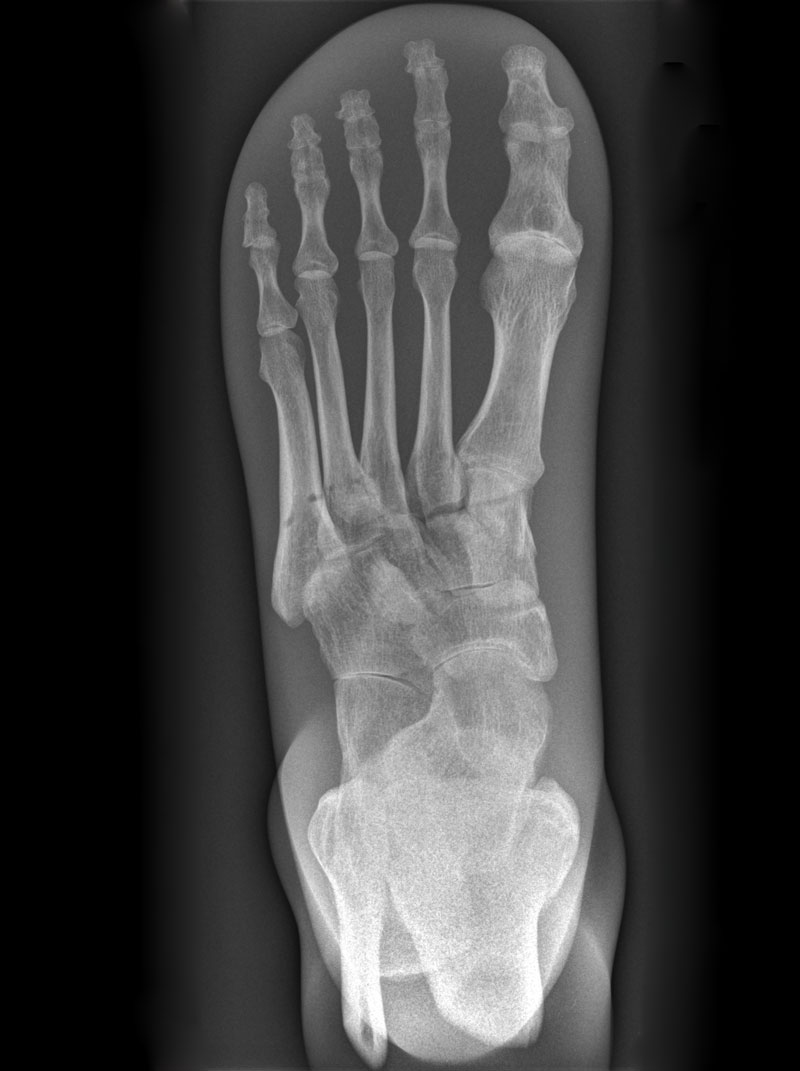

Röntgenphantom Fuß mit Knöchel, transparent

Unsere weltweit einmaligen Röntgenphantome enthalten echte menschliche Skelett - Teile. Dies gewährleistet erstklassige Aufnahmen und realistische Übungsbedingungen. Eine praxisnahe Röntgen - Ausbildung ist ohne diese Modelle nicht möglich. Jedes Modell wird in handwerklicher Einzelstückfertigung hergestellt und ist jeweils ein Unikat. Bedingt durch die Verwendung von echten Knochen und die individuelle Fertigung weichen die einzelnen Modelle in Größe und Beschaffenheit voneinander ab. Auch erhältlich in undurchsichtiger Ausführung (opak), Art.Nr. 7235.

7230 Röntgenphantom Fuß mit Knöchel, transparent

2.785,71 € (3315,00 €)

7235 Röntgenphantom Fuß mit Knöchel, Opak

2.756,30 € (3280,00 €)